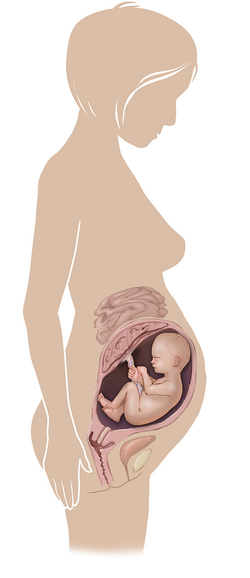

مراحل تطور الجنين أثناء الحمل

تطور الجنين خلال فترة الحمل على ثلاثة مراحل: أول 14 أسبوع من الحمل ، ثم تطوره بداية من الأسبوع 14 وحتى 28 أسبوعا ، ثم الثلث الأخير من 28 إلى 40 أسبوع من الحمل ... المزيد

مراحل تطور الحمل أسبوعيا بالصور

مراحل تطور الحمل أسبوعيا لكل من الأم والجنين داخل الرحم مدعومة بالصور التوضيحية ... المزيد